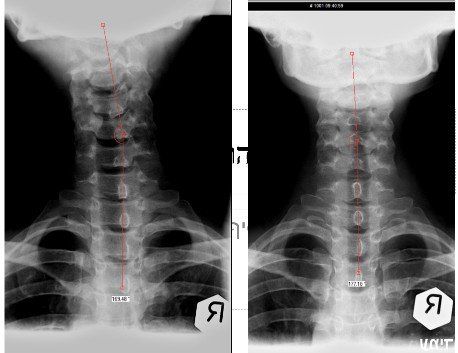

ื"ืจ ื ืืืื ืงืืืข ืืช ืชืืื ืืช ืืืืคืื ืืืืืืฆืช ืืืชืื ืืืกืืืจืื ืืจืคืืืืช, ืืืฆืื ืืืืืงืืช, ืืืฆืื ืจื ืืื, ืกื-ืื ืื ืื-ืืจ-ืืื, ืืืฉืืฉ ืืืืืืช ืืืืืืจ ืฉื ืคืืข ืืืืืื ืืืจืืคืจืงืื ืืื ืืืขืจืื ืขื ืืื ืืฉืคืืข ืื ืืง ืืขืืื ืืฉืืืจื ืขื ืืขืจืืช ืืขืฆืืื ืืืจืืืืช ืืืืฃ. ืืฉืื ืืืืืจ ืฉืชืคืงืื ืืืืจืืคืจืงื ืืื ืืืกืืจ ืกืืืืงืกืฆืื (ืชืช ื ืงืืขื ืฉืืจืชื) ืฉืืคืจืืข ืืืืฃ ืืชืคืงื ืืืืคื ืืืคืืืืื. ืชืืืื ืจืืคืื ืืจืงืืืช ืืื ืืืขื ืืืชืืคืฉืจ ืืชืื ืืืืฃ ืขืฆืื. ืืืืฃ ืืฉ ืืืืืช ืจืืคืื ืืืขืืช ืืืืืืขืช ืืืจืงื ืืื ืื ืืฉืื. ืืืืืื ืืืืจืืคืจืงืื ืืกืืจ ืืืฅ ืืืืขืจืืช ืืขืฆืืืช ืข"ื ืฉืืคืืจ ืชืคืงืื ืขืืื ืืฉืืจื, ืืืืคืฉืจ ืืื ืจืืื ืืขืฆืืืช ืืืฉืชืืฉ ืืืืืืืช ืืืืฃ ืืืืขืืืช ืืืืืื. ืจืคืืื ืืืชืืช ืชืืื ืืื ืืืื ืืืืื ืืชืื ืืืืฃ ืขืฆืื. ืชืงืฉืืจืช ืืื ืืืื ืืืืฃ ืืืืจื ืืื ืืืืฃ ืืืื ืืืื ืืช ืืงืืื ืืืืฃ ืืืจืืืืชื. ืคืืื ืฆืืื ืืืจืืืืช ืืืืืช ืื ืจืืืืช ืืืืื ืฉืืืืฃ ืืืื ืืืืืข ืชืืืืื ืืืจืืืืช ืขืืื ืืฉืืจื ืืืืขืจืืช ืืขืฆืืืช ืฉืคืืขืืื ืืื ืืคืจืขืืช ืืืชืืื.

ืืืืคืื ืืืืจืืคืจืงืื ืืืื ืืช ืืืืฃ ืืืืจืืฅ ืืช ืื ืจืืืืช ืืืืื ืืชืืื ืืืืืื.